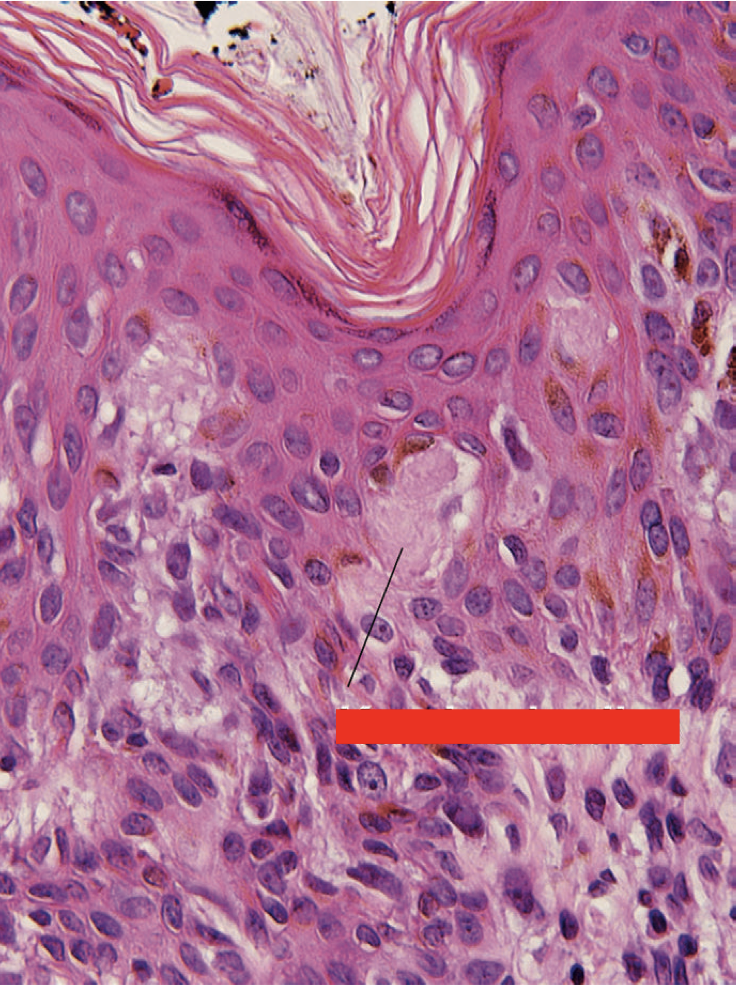

Identify. What condition is this seen?

Civatte Bodies

Lichen Planus